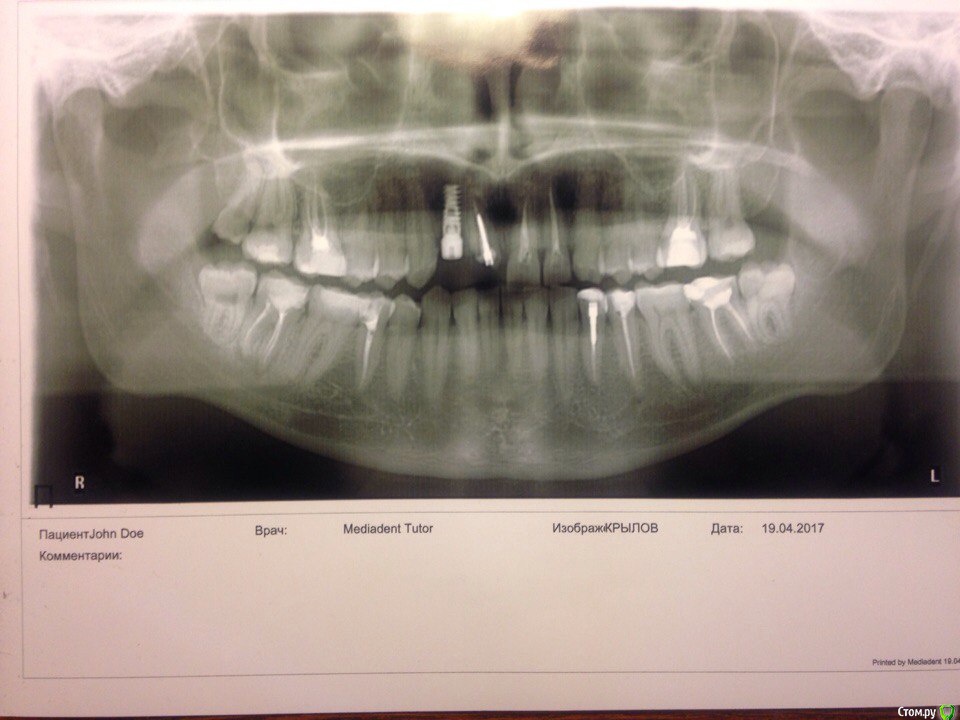

Сделал рентген всей челюсти.post-51349-0-65805200-1492620709_thumb.jpg

В день когда я записался к хирургу, который мне устанавливал имплант, протез выпал совсем. Голова стала болеть немного меньше, но все равно болела. По настоянию врача сделал прицельный рентген где установлен сам имплант и КТ всей челюсти для определения кисты.post-51349-0-78543900-1492620486_thumb.jpg post-51349-0-84336600-1492620557_thumb.jpg Я все сделал и врач установил, что имплант стоит прочно и следует просто заново поставить протез, но лучше по отдельности(не общий для 2 зубов). На КТ кисту он тоже нашёл и направил к челюстному-лицевому хирургу. Поставил мне временный штифт(не знаю как назвать), и на следующий день голова опять начала болеть как прежде.